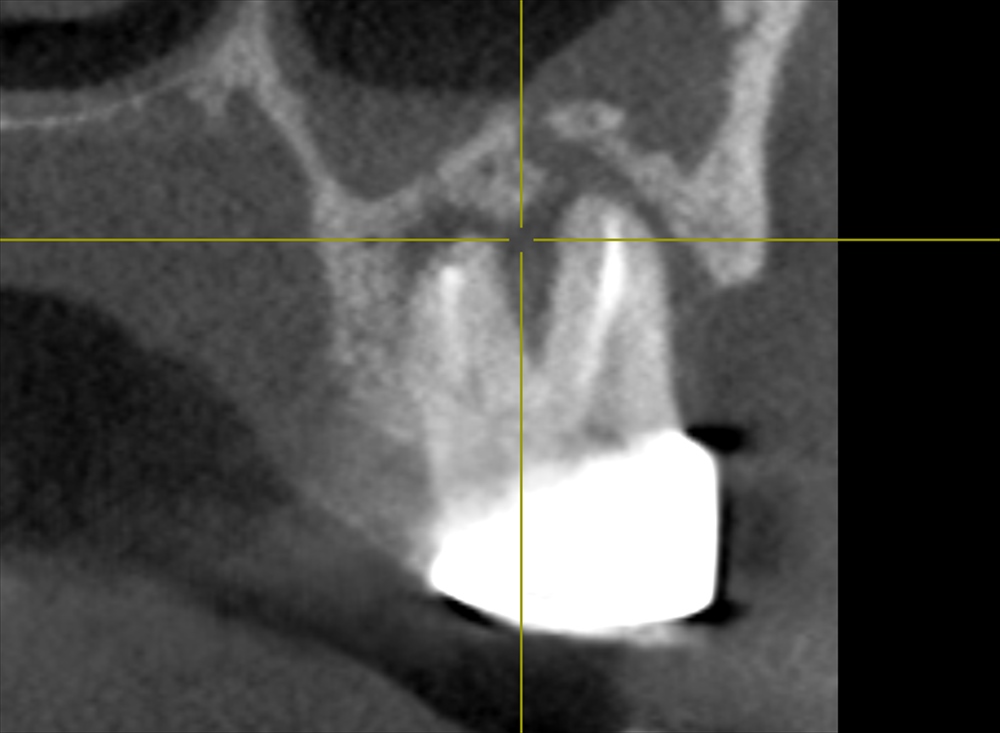

歯科ドック(CT)鼻の部屋にまで広がる重症の虫歯を発見。骨が溶けています。

①根尖性歯周炎

②咬合性外傷(かみ合わせ)

③歯周病

の3つの原因がありました。歯科ドックを行わなければわかりませんでした。このお話を丁寧に患者さまへ説明しご理解いただいた上で治療をスタートいたします。